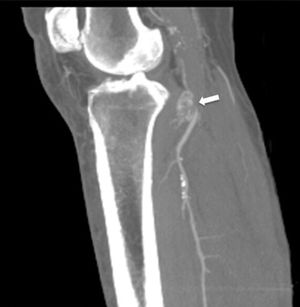

A male, 67 years of age, obese, with high blood pressure and dyslipidemia presented at the emergency department due to pain, cold and functional impairment of his lower left limb of 24-h onset. During anamnesis, the patient stated he had had a chronic intermittent pain in his left knee for a long time. A previous simple knee X-ray showed an osteochondroma (Fig. 1). The patient presented with a femoral pulse but with no popliteal and distal pulses. Artery examination was normal in the contralateral extremity. A CT angiogram was requested for the lower limbs which showed thrombosis of the popliteal artery adjacent to the osteochondroma (Figs. 2 and 3). We decided to perform in situ revascularization with femoro-popliteal saphenous vein graft (Fig. 4) avoiding the tunneling technique for anatomical positioning. To date, after 3 years of follow-up with eco-Doppler, the bypass continues maintaining permeability with ankle-arm index of 0.9, and no signs of popliteal vein injury.

Osteochondroma is the most common pseudotumoral bone lesion. The radiologic pathognomonic characteristic of this tumor is the cortical and medullar continuity of the lesions with the bone from which they protrude.1 They may be single or multiple.2 Some of the most common complications are the presence of bone deformity, fractures,1 vascular compromise3 and neurological compromise,4 formation of a bursa5 and malignant degeneration.6 Diagnosis may be made with an X-ray, although other imaging methods such as a scan, CT and MR may be used in suspected cases when symptoms occur or are in unusual locations.1 Vascular compromise may be caused by displacement of blood vessels (arteries and veins), by stenosis, occlusion and the formation of pseudoaneurisms, with the latter being more frequent at knee level,7 involving the popliteal artery or being presented as arterial thrombosis,8,9 as in this clinical case. Its presentation as thoracic outlet syndrome in the case of rib lesions has been described.10